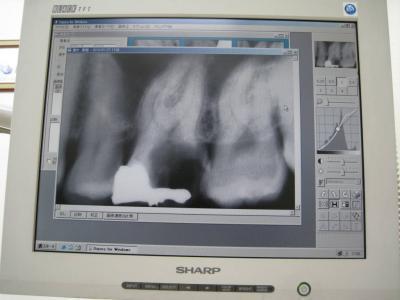

レントゲン写真です。

会社の検診医なので「レントゲン写真撮らせろ!」って言ったら撮らせてくれました ^^;

普通はこんなの撮らせてくれないんだろうけど・・・。

私を数ヶ月間悩ませ続けた歯のレントゲン写真。

奥歯の一番重要な歯が半分近く欠けているのがわかりますか?

真っ白な部分が詰め物をしたところ、薄白い部分が歯ですが

歯があるべきところが黒っぽくなってる。

そこが欠けて虫歯の原因になったところです。